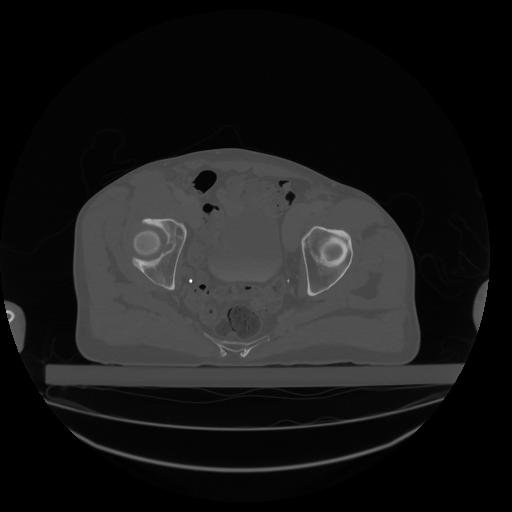

34 CUERPO,CE,Vol,1.0,CUERPO,,